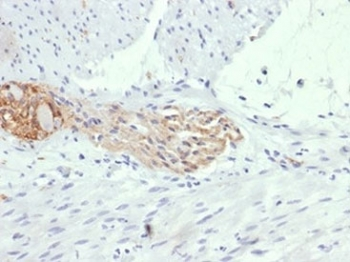

| Description | Mouse monoclonal antibody to CD56 (NCAM1) |

| Tested applications | IHC, WB |

| Dilution range | WB 1:2000, IHC 1:150 |

| Target | CD56 |